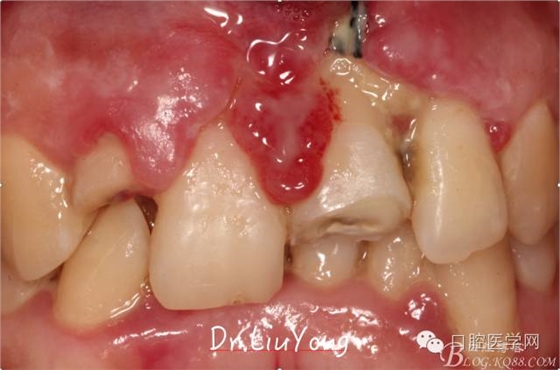

檢查:面部對(duì)稱無(wú)腫脹畸形,張口度正常,口內(nèi)檢查可見(jiàn)A2牙冠缺失,可見(jiàn)直徑約1.5mm左右穿髓孔,冷熱刺激痛+,叩痛+,探痛+,近中斷面探診位于齦下1.5mm,A1B1B2松動(dòng)2-3度,B1牙冠缺失1/2,冷熱刺激痛-,叩痛+,B2牙冠完整,A2-B2牙齦紅腫,探診極易出血,全口口腔衛(wèi)生差,牙結(jié)石++,A1B1之間牙齦乳頭紅腫嚴(yán)重,B1唇側(cè)牙齦萎縮明顯,牙齦邊緣可見(jiàn)縫線兩處,局部有滲出,齦緣冠方1mm處見(jiàn)白色骨塊,松動(dòng),觸痛明顯,觸及骨塊時(shí)可見(jiàn)B1及B2近中唇側(cè)牙齦動(dòng)度,B1B2之間唇側(cè)牙齦乳頭缺失,B2近中根面可見(jiàn)大量牙結(jié)石。重度深覆合,牙尖交錯(cuò)位時(shí)C3-D2咬至上前牙腭側(cè)齦緣,A1切端咬至C12唇側(cè)齦緣。其余牙齒未見(jiàn)明顯異常。

術(shù)前口內(nèi)照片如下: